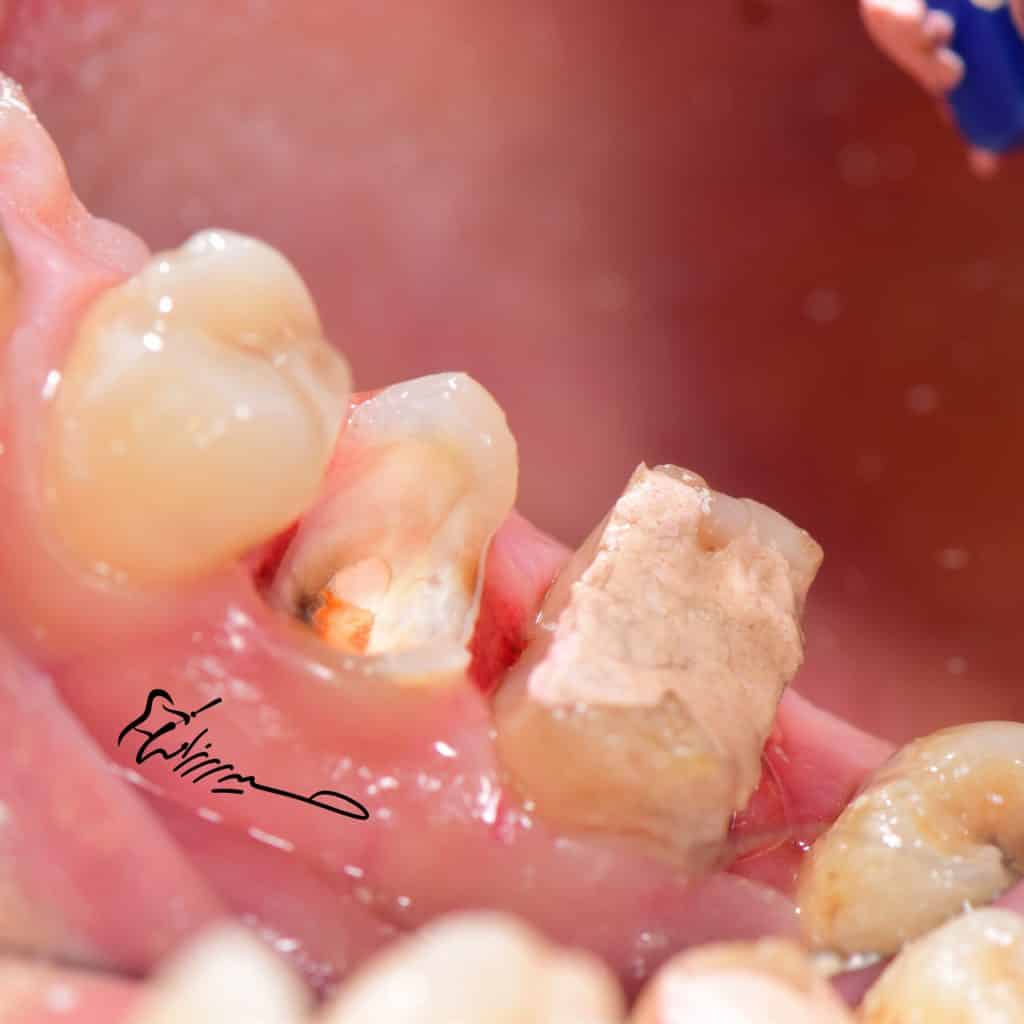

deep margin must elevate

destructive structures and there is no feruule

so adhesive options are the best